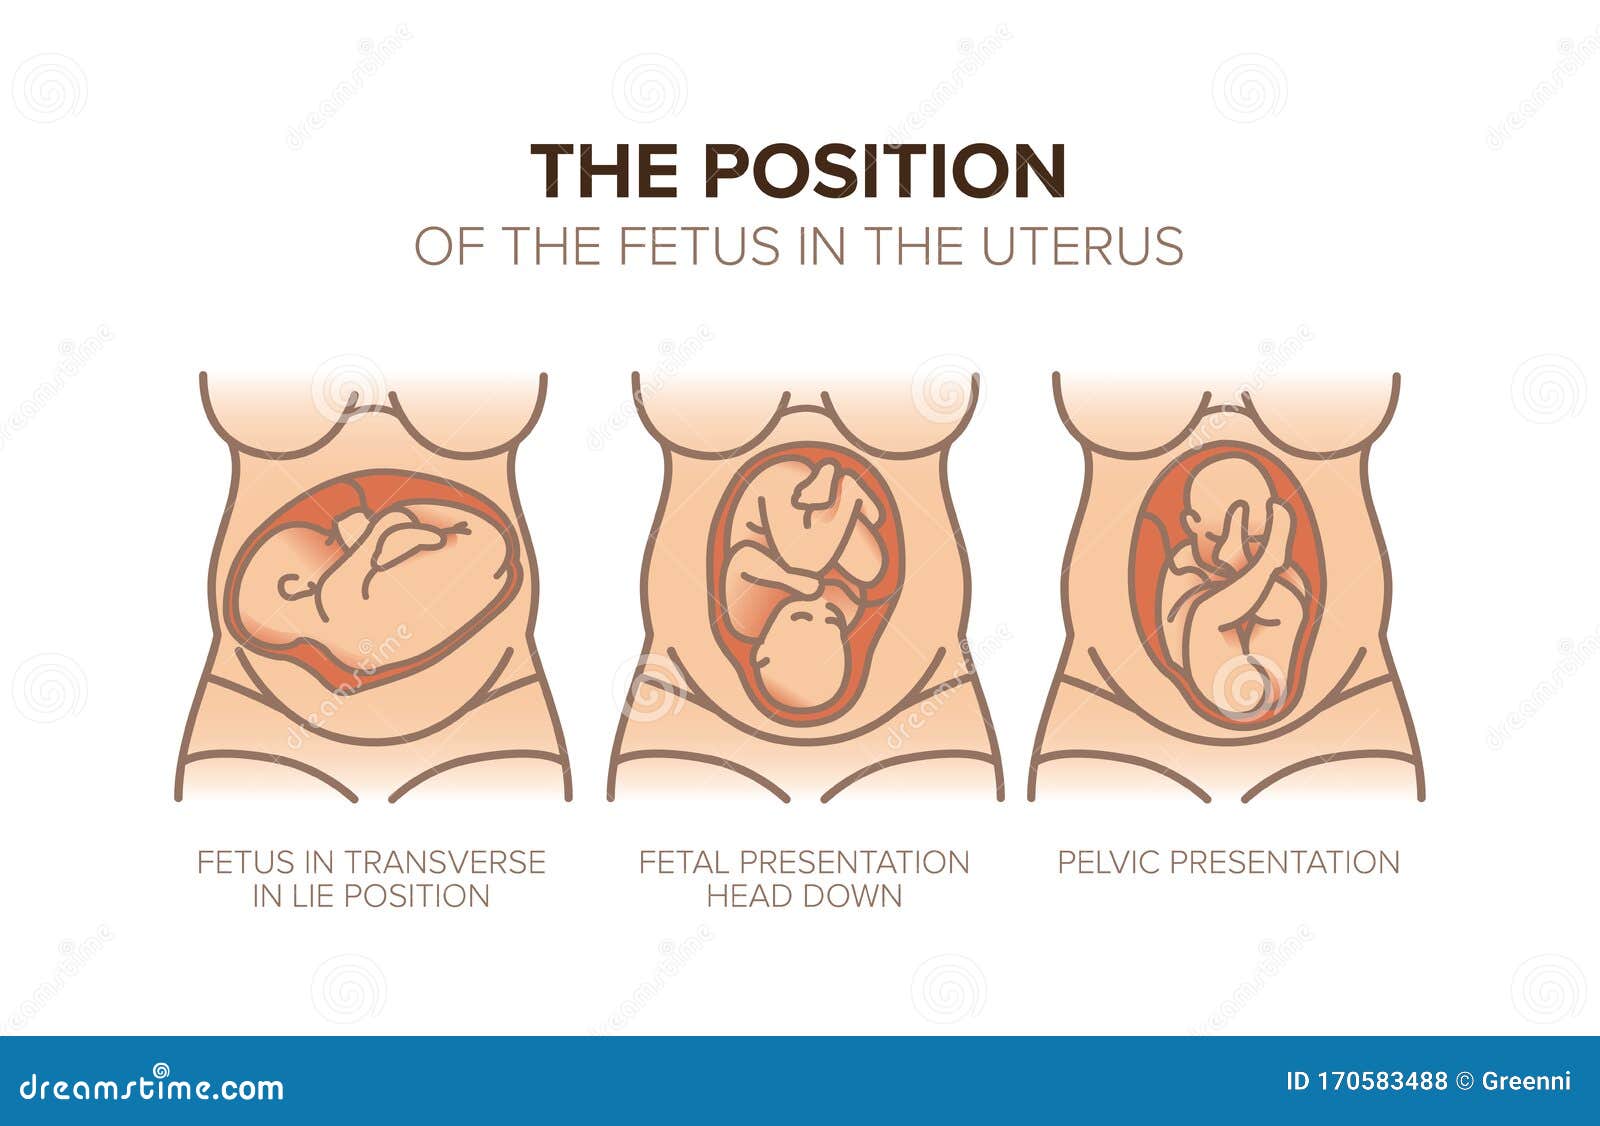

Во время беременности, положение плода имеет большое значение для мамы и малыша. Одним из типичных положений является продольное предлежание головное. В этом положении голова малыша находится внизу, а ножки - наверху. Это положение достаточно распространено и предпочтительно для естественных родов.

Расположениребенка в матке

Карта положения ребенка в утробе

Расположение ребенка в матке